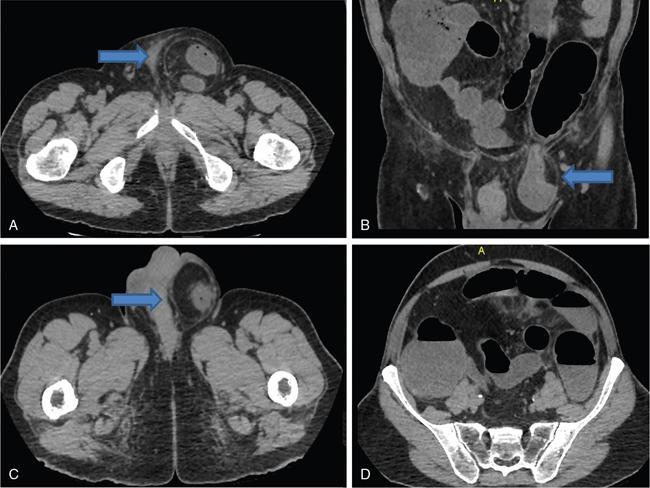

Amandeep Singh The abdominal wall surrounds the anterolateral aspect of the abdominal cavity, where many important organs are located. The abdominal wall is made up of: Superior epigastric artery, inferior epigastric artery, deep circumflex iliac vessels, superficial epigastric vessels and superficial circumflex iliac vessels supply the anterior abdominal wall. Nerves of the anterior abdominal wall include subcostal nerve, iliohypogastric and ilioinguinal nerves. Types of abdominal hernias: The diagnosis of hernia can be made with plain radiographs, barium studies and CT. They consist of a peritoneal sac which protrudes through a weakness/defect in the muscular layers of the abdominal wall (mainly in transversalis fascia below the conjoined tendon). Preperitoneal fat, greater omentum and viscera may protrude into the sac (Fig. 7.15.2). Types: Indirect or direct (depending on their relationship to the inferior epigastric vessels). Indirect hernia: They occur in infants and children. The peritoneal sac passes through the internal ring into inguinal canal, lateral to the inferior epigastric vessels and anterior to the spermatic cord. In women, it goes along the round ligament into the labium. Rarely, the herniated sac instead of leaving the external inguinal ring continues along with the abdominal wall muscles. This is called interparietal hernia (Fig. 7.15.3). Direct hernia: It is always acquired. The herniated sac is medial to the inferior epigastric vessels and does not pass through the inguinal canal. Hence, they do not reach up to scrotum. Femoral hernias are less common than inguinal hernias. They are more common in paediatric age groups and women. The predisposing feature is the empty space between the lacunar ligament medially and the femoral vein laterally. Physical changes of pregnancy dilate this space. The herniated sac is below the inguinal ligament and lateral to the femoral vessels. Strangulation is a common complication. In femoral hernia, the sac lies below and lateral to the pubic tubercle as it emerges from the femoral canal. It can be differentiated from an inguinal hernia which lies above and medial to the pubic tubercle (Fig. 7.15.4). Incisional hernias occur as a result of complication of laparotomy. Risk factors include old age, obesity, postoperative wound infection, chronic pulmonary disease, cirrhosis, malignant tumour, steroids and malnutrition. Most of these hernias develop during the first few months after surgery but may remain silent for up to a period of 5 years. Incisional hernia are more likely to occur as a result of vertical incisions than transverse incisions. They may occur following incisions as small as a puncture site for laparoscopic surgery. A common variation is the parastomal hernia, in which bowel and omental fat protrude through a defect immediately adjacent to an ileostomy or colostomy opening. Bowel loops may be incorporated into the hernia and become incarcerated or strangulated, if the hernia is not treated (Fig. 7.15.5). Richter’s hernia is a rare type of hernia which includes only a part of the bowel wall. Because only a portion of the intestinal wall is included into the hernia, therefore, the lumen remains patent and does not result in obstruction. However, incarceration is not common. Any hernia which contains a Meckel’s diverticulum is known as Littre hernia. They may occur due to the presence of inflammatory adhesions that cause confinement of the Meckel’s diverticulum within the hernia sac. Approximately 50% of Littre hernias develop in the inguinal region, 20% in the femoral, 20% in umbilical and 10% in other sites. Spigelian hernia is a rare acquired ventral hernia that occurs through the linea semilunaris, the line where lateral rectus sheath is formed by fusion of sheaths of lateral abdominal muscles. They are almost always found just above the point where posterior wall of the rectus sheath is pierced by the inferior epigastric vessels. It occurs at midpoint between the umbilicus and symphysis pubis, which is a weak point along the lateral border of the rectus muscle. They are rare but have a high frequency of incarceration and strangulation. It may be mistaken for an abdominal wall lipoma, if it contains only peritoneal fat. CT can be quite beneficial to confirm the diagnosis (Fig. 7.15.6).